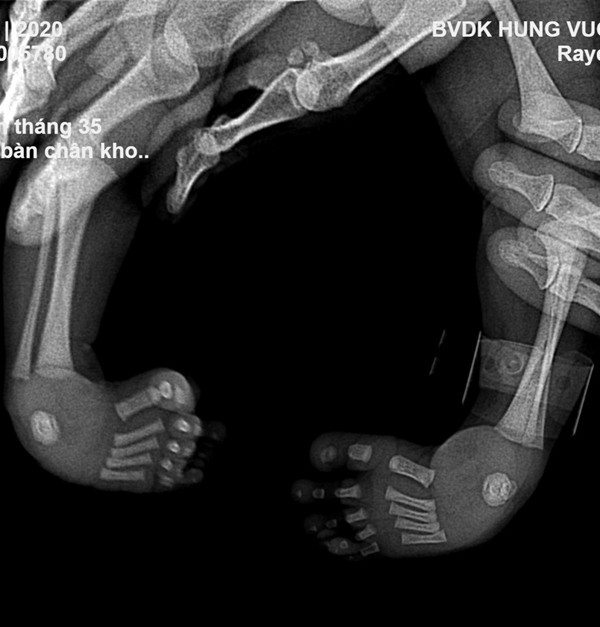

Đặc biệt, một bé bị dị tật khoèo bẩm sinh, 2 bàn chân cong hướng vào nhau. Nếu không điều trị, sau này sẽ rất khó khăn vận động.

Sau khi hội chẩn, các bác sĩ khoa Chấn thương chỉnh hình quyết định can thiệp điều trị cho bé bằng phương pháp Ponseti nắn chỉnh nhẹ nhàng, bó bột để duy trì kết quả nắn.

Các bước nắn và bó bột này được lặp lại mỗi tuần, trong vòng 6-8 tuần liên tiếp giúp bàn chân dần dần trở về hình dạng bình thường.